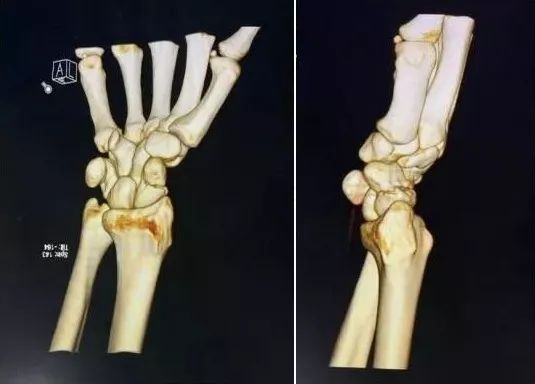

6)桡骨远端骨折

图片

• 绝大部分骨折可以手法复位制动。

• 关节面粉碎,塌陷者应手术。

• 如果伤后拇长伸肌腱卡压,正中神经损伤者,应立即手术。